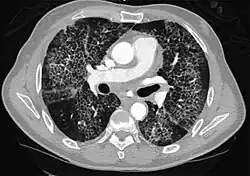

High-Resolution CT image in a patient with Pneumocystis pneumonia infection showing ground-glass opacities.